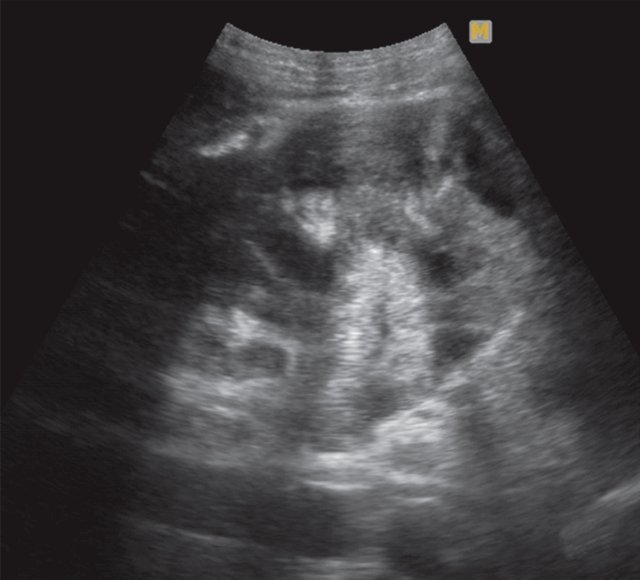

При УЗИ почки расположены типично, в размерах не изменены. Подвижность при дыхании сохранена, контуры ровные, четкие. Полостная система не расширена, мочеточники не визуализируются. В проекции нижней группы чашечек справа визуализируется тканевой плотности гипоэхогенное образование размером до 40 мм (рис. 9). Заключение: "объемное образование правой почки".

В проекции полостной системы визуализируется тканевой плотности гипоэхогенное образование размером до 40 мм.